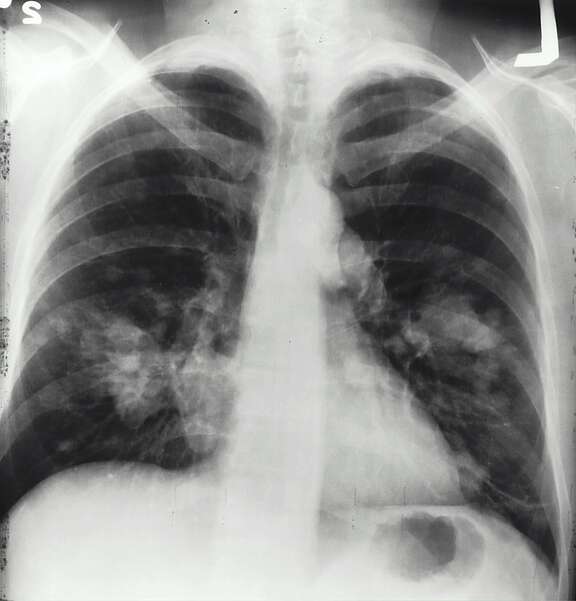

- Les maladies pulmonaires dues au tabac